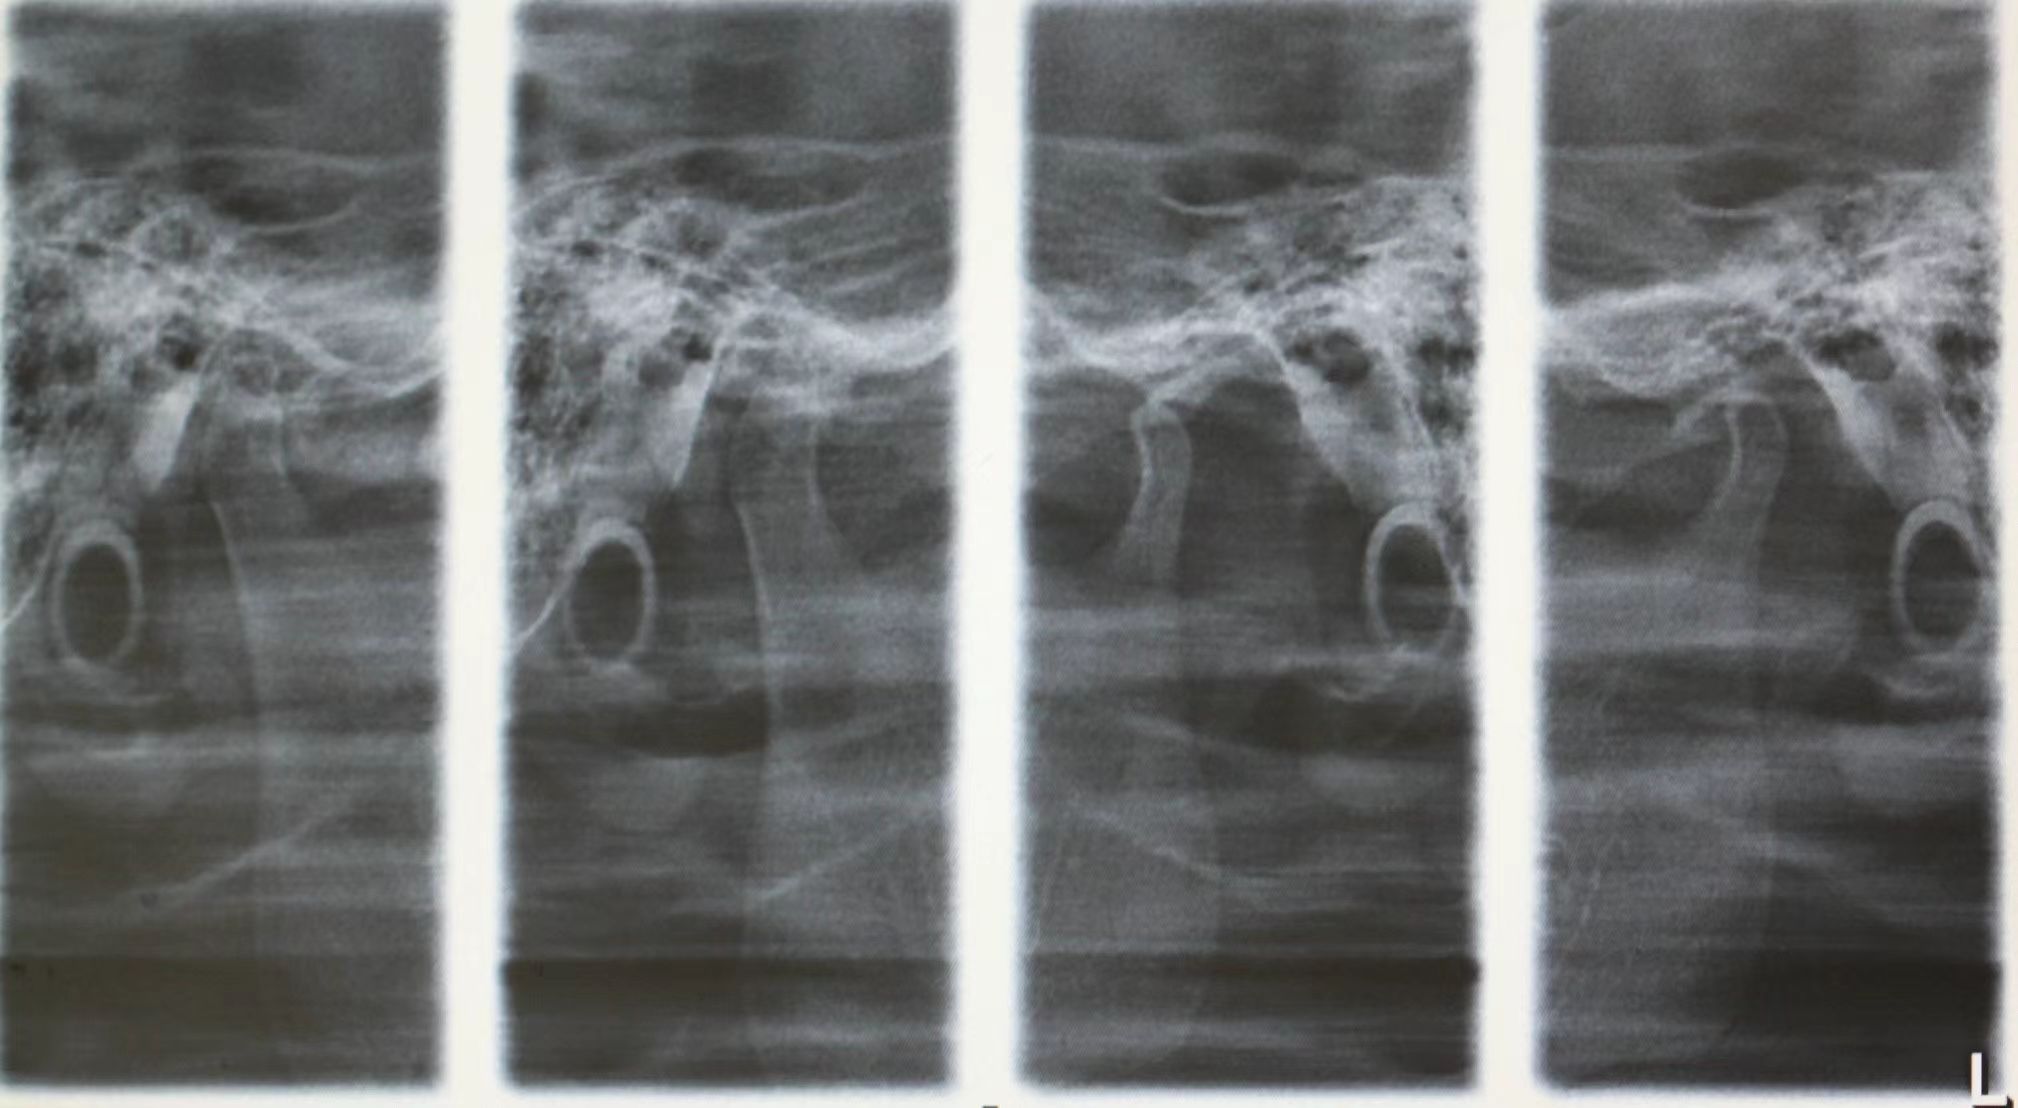

情况:不接受外科手术,在当地做了1年半的矫治,遇到困难无法进行。由外地正畸同行推荐来上海寻求非手术矫治的二手病例。武广增老师接收时的错合畸形情况,呈现严重的骨性反合偏合及侧方开合(图1-图10)。由于推荐其去口腔医院接受正颌外科手术遭到拒绝,武广增老师通过专业的检查、分析,制定一套详细的治疗计划,采用了磨牙推进器技术、武式辅弓技术等特色正畸手段获得明显效果(图2-1~图2-9)。治疗结束后也拍摄了相关照片(图3-1~图3-9)。

矫治前

图10